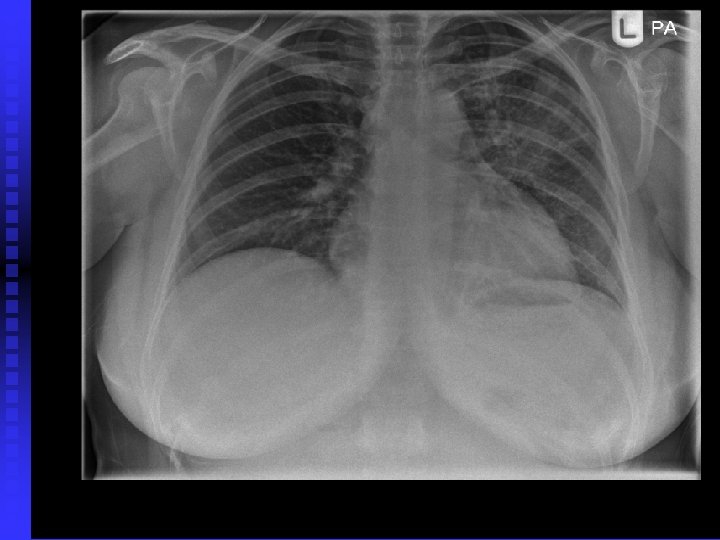

Case 2 40 year old woman, non smoker n Persistent productive cough despite several courses of antibiotics n CXR abnormality: not resolving after several weeks n Admitted to hospital with severe SOB and chest pain n Found to have extensive CXR changes and pericardial effusion n

Case 2 Pericardial effusion drained (pericardial window) n Bronchoscopy and BAL: bronchoalveolar cell carcinoma n Stage 4 disease n Referred for palliative chemotherapy n

Bronchoalveolar cell carcinoma n Presents with increasing breathlessness, productive cough n CXR: pneumonic process (alveolar shadowing) n Usually peripheral n Chemotherapy n Poor prognosis